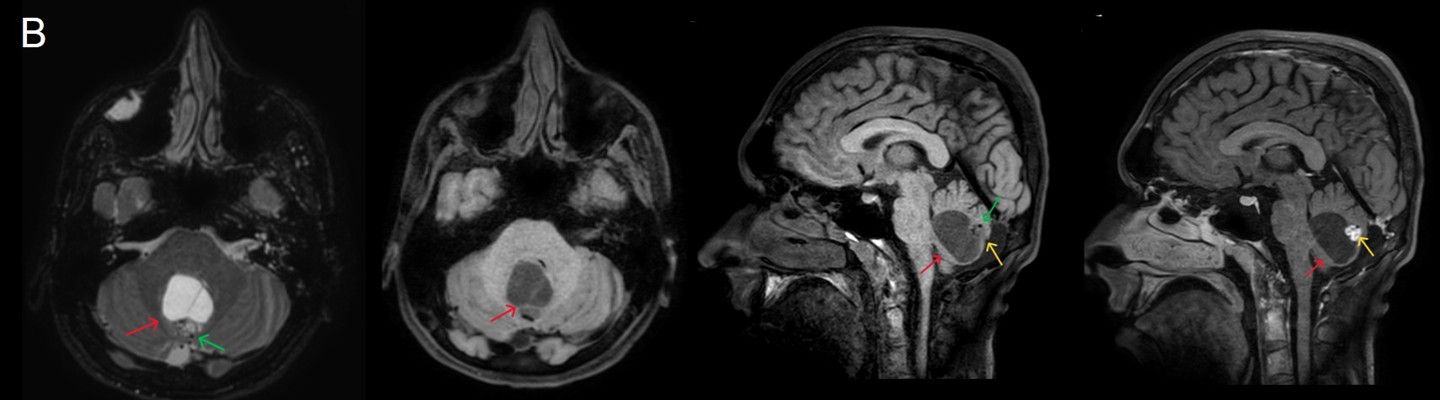

- B) Beyin MRG incelemesinde; 4. ventriküle bası etkisi oluşturan yaklaşık 3.5 cm boyutta, T2A hiperintens T1A hipointens kistik komponent (oklar) ve posteriorunda T1 ve T2A serilerde parankim ile izointens, içerisinde flow void alanların (oklar) izlendiği, post kontrast görüntülerde yoğun kontrast tutulumu gösteren mural nodül (oklar) barındıran düzgün sınırlı lezyon izlenmektedir.

- Kistik komponent: T1A hipointens, T2A hiperintens

- Mural nodül: T1A izo-hipointens, T2A orta derecede hiperintens olabilir.

- Kontrastlı incelemelerde mural nodül belirgin ve yoğun kontrast tutulumu gösterir. Ancak kist duvarında genellikle kontrastlanma beklenmez.

- T1 ve T2A görüntülerde flow voidler sıktır.